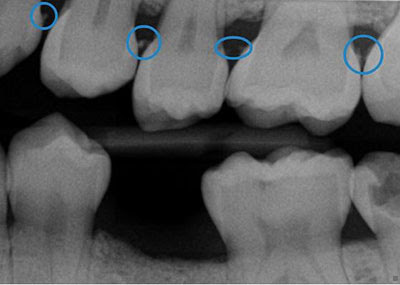

Now I have holes between my teeth and gums , mostly in my front teeth, and it looks very unattractive when i smile. Do receding gums grow back ? Receding Gums Treatment Options. This process includes scraping away of the tartar from your teeth and under the gum line- this is often done with an ultrasonic device that uses vibrations to remove plaque. So, do gums grow back ? If the pockets remain deep and inflamed after this treatment, surgery may be the only solution to put the gums back into place, securely around the tooth.

In this case home remedies will help your gums grow back. The receding gums whether to grow back or not usually depends on severity of the condition, although this reverse process is not usually compete up the usual state. If you do develop gum disease, however, giving your teeth deep cleaning can remove the infection and tartar so your gums can heal. When a deep cleaning is performed by a dentist, the tarter is removed from the pockets leaving them clean, the pockets are treated with direct antibiotics, the gum becomes healthier and more pink in color. Aside from easing the disorder, deep cleaning also helps prevent gum disease from becoming more severe.

Based on your description, it is not probable that your gums will fill in the spaces between your teeth. Deep cleaning is a non-invasive and non-surgical procedure.